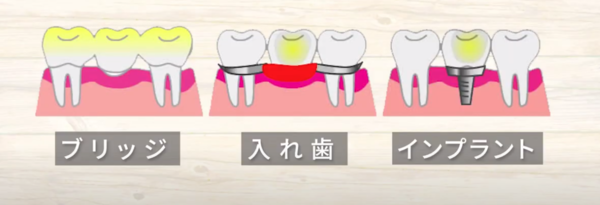

歯を抜いた後の治療方法

として

ブリッジ

入れ歯

インプラントか

悩まれる方、多いかと思います。